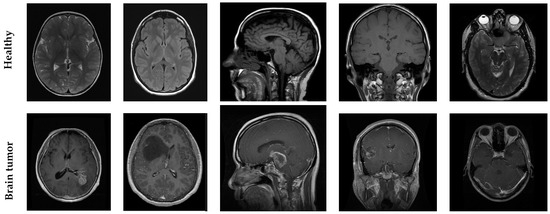

Figure 2 displays representative samples from each class, illustrating not only the variability and characteristics inherent in both the healthy and tumor-affected brain scans but also the impact of this diversity. The presence of different anatomical planes and shifts plays a critical role in improving the model’s capacity to adapt and perform reliably across a wide range of clinical cases.

Figure 2. Example MRI images from the dataset used in this study. The top row shows MRI scans of healthy brain tissue, while the bottom row depicts scans with visible brain tumors. Each row includes different views, such as axial, coronal, and sagittal planes, demonstrating the anatomical differences between healthy and pathological cases.